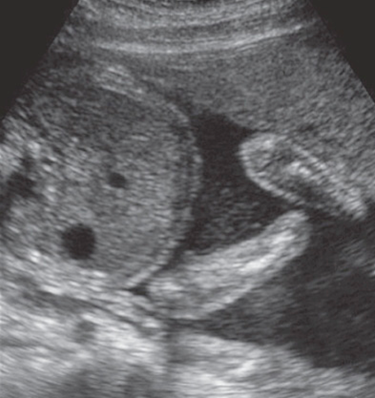

Fetal ascites